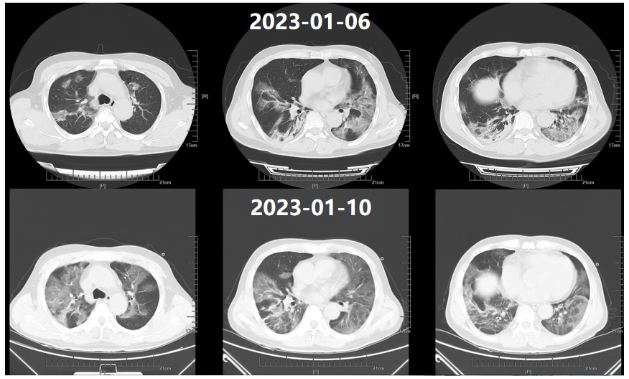

新冠病区诊治过程:鼻导管吸氧;阿兹夫定5 mg qd抗病毒、莫西沙星0.4 g qd抗感染,丙球10 g qd,地塞米松6 mg×2 d,之后予甲泼尼龙40 mg bid抗炎,低分子肝素钠5000单位ih q12h抗凝等治疗。2023年1月10日胸闷气急症状加重。血气分析(FiO2 41.0%):pH 7.39,PaO2 35.6 mmHg,PaCO2 34 mmHg,氧合指数87 mmHg。胸部CT(2023年1月10日,我院):双肺斑片影,符合病毒性肺炎,且较2023年1月6日明显加重(图1);双肾萎缩;双肾结石。

图1  患者胸部CT